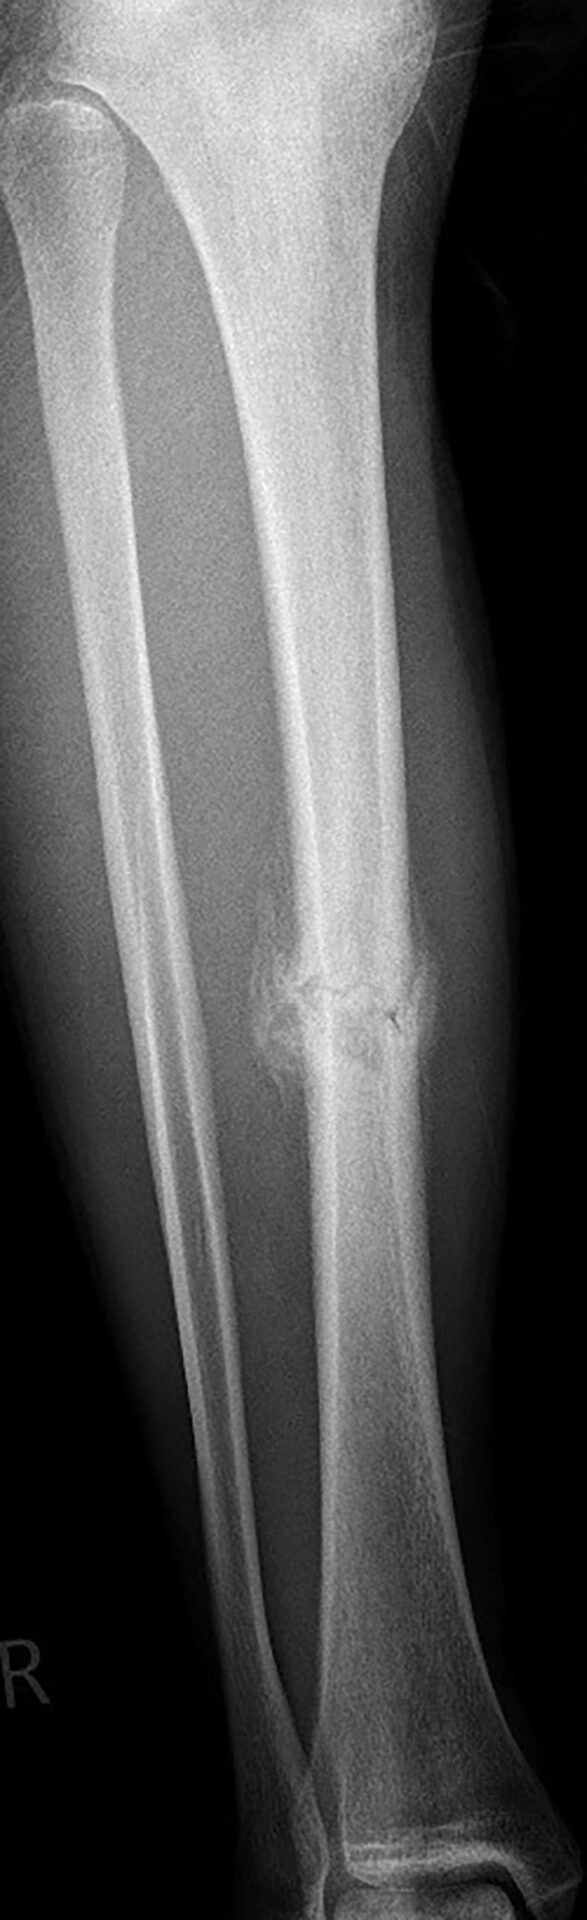

Torwart, 1. Regionalliga, Tibiaschaft(re)fraktur

In einem Freundschaftsspiel zweier Amateurligavereine kam es zwischen Torwart und Gegenspieler im Kampf um den Ball zu einem Frontalzusammenstoß mit offener Sohle. Der Torwart beschrieb, extreme Schmerzen im Bereich der rechten Tibiakante zu haben (NRS 8/10). Er konnte zu demonstrativen Zwecken das Bein leicht belasten und hierbei eine unphysiologische Wippbewegung im schmerzhaften Bereich provozieren. Für den Transport ins Krankenhaus wurde die Tibia stabil getaped und mit einem Cryo-Kompressionsverband versorgt. Das Röntgenbild zeigte eine Tibiaschaftfraktur, eine Schrägfraktur mit gerade verlaufender Frakturlinie (Abb. 1).

nach Röntgen Unfallgeschehen

Der Spieler wurde stationär aufgenommen und erhielt neben Antikoagulationstherapie und Novalgin eine Oberschenkelgipsschiene und Unterarmgehstützen. Mit verschiedenen Ärzten evaluierte der Spieler Pro und Contra operativer und konservativer Therapie. Nach zwei Tagen entschied er sich gegen eine OP und wurde nach Hause entlassen. Voraussetzung hierfür war konsequente Ruhe, Hochlegen des Beines und eine wöchentliche Röntgenkontrolle, um Achsabweichungen im Knochenheilungsprozess erkennen zu können. Ab der 2. Woche begann die Physiotherapie. Um den Abtransport der Schwellung, welche sich deutlich im Sprunggelenk und Fuß abgelagert hatte, zu unterstützen, wurde der Unterschenkel mit Grifftechniken aus der manuellen Lymphdrainage behandelt. Das Bein wurde dabei nicht aus der Schiene bewegt. Außerdem benutzte der Spieler eigenständig ein EMS-Gerät, welches er hauptsachlich auf den Quadriceps applizierte. Nach drei Wochen erhielt der Spieler eine Sarmiento-Brace, welche in einem speziellen Orthopädiefachgeschäft maßangefertigt wurde. Diese sollte er weitere drei Wochen tragen. Parallel dazu lag der Fokus weiterhin auf Krafterhaltung der Rumpfmuskulatur und Resorptionsförderung der Schwellung. Nach sechs Wochen konnte der Spieler mit 15 kg die Teilbelastung starten. Als er nach sechseinhalb Wochen mit den Gehstützen auf nassen Badfliesen ausrutschte, kam es zu einer erneuten kurzfristigen Schmerzprovokation und deutlichen Schwellungszunahme in der ventralen Tibia. Das Röntgenbild zeigte keine Verschiebung der Fraktur (Abb. 2). Jedoch wurden Zeichen einer Refrakturierung wurden im Röntgenbild zwei Wochen später sichtbar (Abb. 3). Schwellung und Schmerz waren inzwischen wieder deutlich reduziert und es konnte weiter langsam mit der Aufbelastung auf 30 kg Teilbelastung gestartet werden. Zusätzlich erhielt der Spieler ein Exogen Gerät zur Ultraschalltherapie zu Hause, welches er täglich 20 min verwendete. Zehn Wochen post-injury, damit vier Wochen post re-injury, konnte der Spieler die komplette Belastung wieder aufnehmen. Die Verwendung des Gerätes läuft aktuell täglich über 20 min weiter und unterstützt den Spieler nach subjektivem Empfinden deutlich bei der weiteren Behandlung. Zusätzlich zu der Behandlung wurde dem Spieler während des gesamten Verlaufs eine Substitution von Vitamin D + Vitamin K empfohlen.